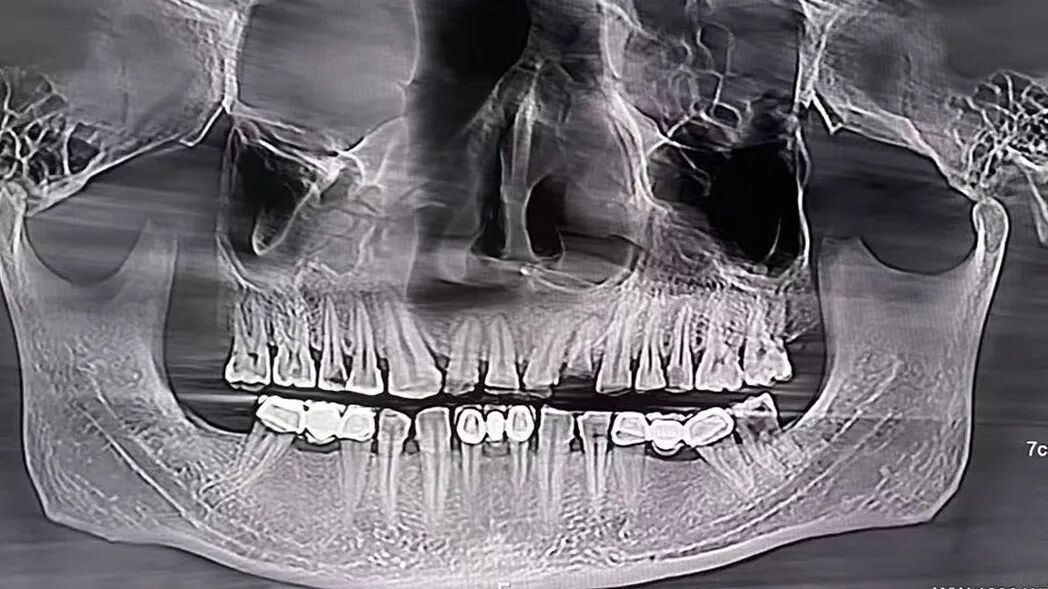

虽然拍单次CT比拍单次X片的辐射剂量高,有“做一次CT相当于拍几十到几百次X光”的说法,但做一次低剂量胸部CT的辐射量约1mSv,口腔CT这类局部检查辐射量更低。

口腔锥形束CT(左图)

口腔CT拍摄的CT影像(右图)

我院的320排CT、口腔锥形束CT西门子数字化X线机都是超低剂量辐射,不管是拍CT、冠脉CTA还是牙片、X片等,辐射剂量都在标准范围内。